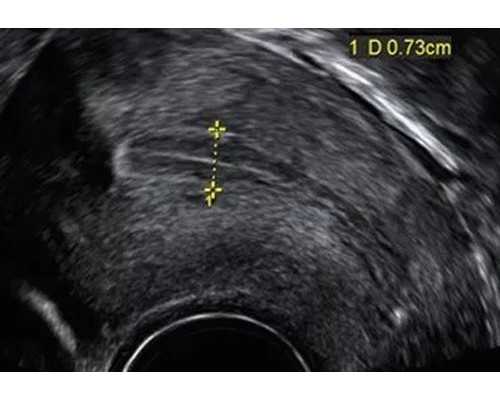

(3)泰国试管失败率高,有的家庭是因为术前身体检查没有做到位,比如说,女方检查激素水平(性激素六项),以及子宫和卵巢的情况(如子宫内膜、肌瘤以及卵巢大小等方面);男性进行精液分析情况等等环节,均没有做到位,导致泰国试管助孕失败。